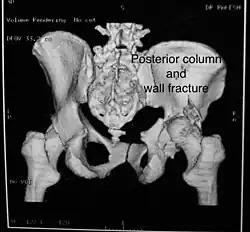

Posterior column and wall fracture as seen on 3D CT -

Posterior column and wall fixed using screws and plates

Combined both column fractures | These are the most complex injuries. Here the weight bearing roof or dome of the acetabulum is a floating piece. This adds to complexity of management.

All three x-ray views plus CT scan is a must for diagnosis and management of this complex injury.